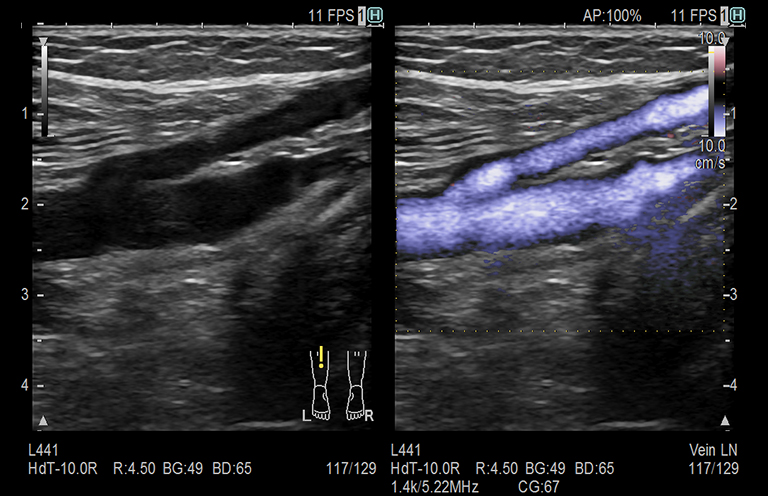

Aplicación: Vascular

Función/Análisis: eFLOW (CF doble)

Comentarios: Extremidad inferior